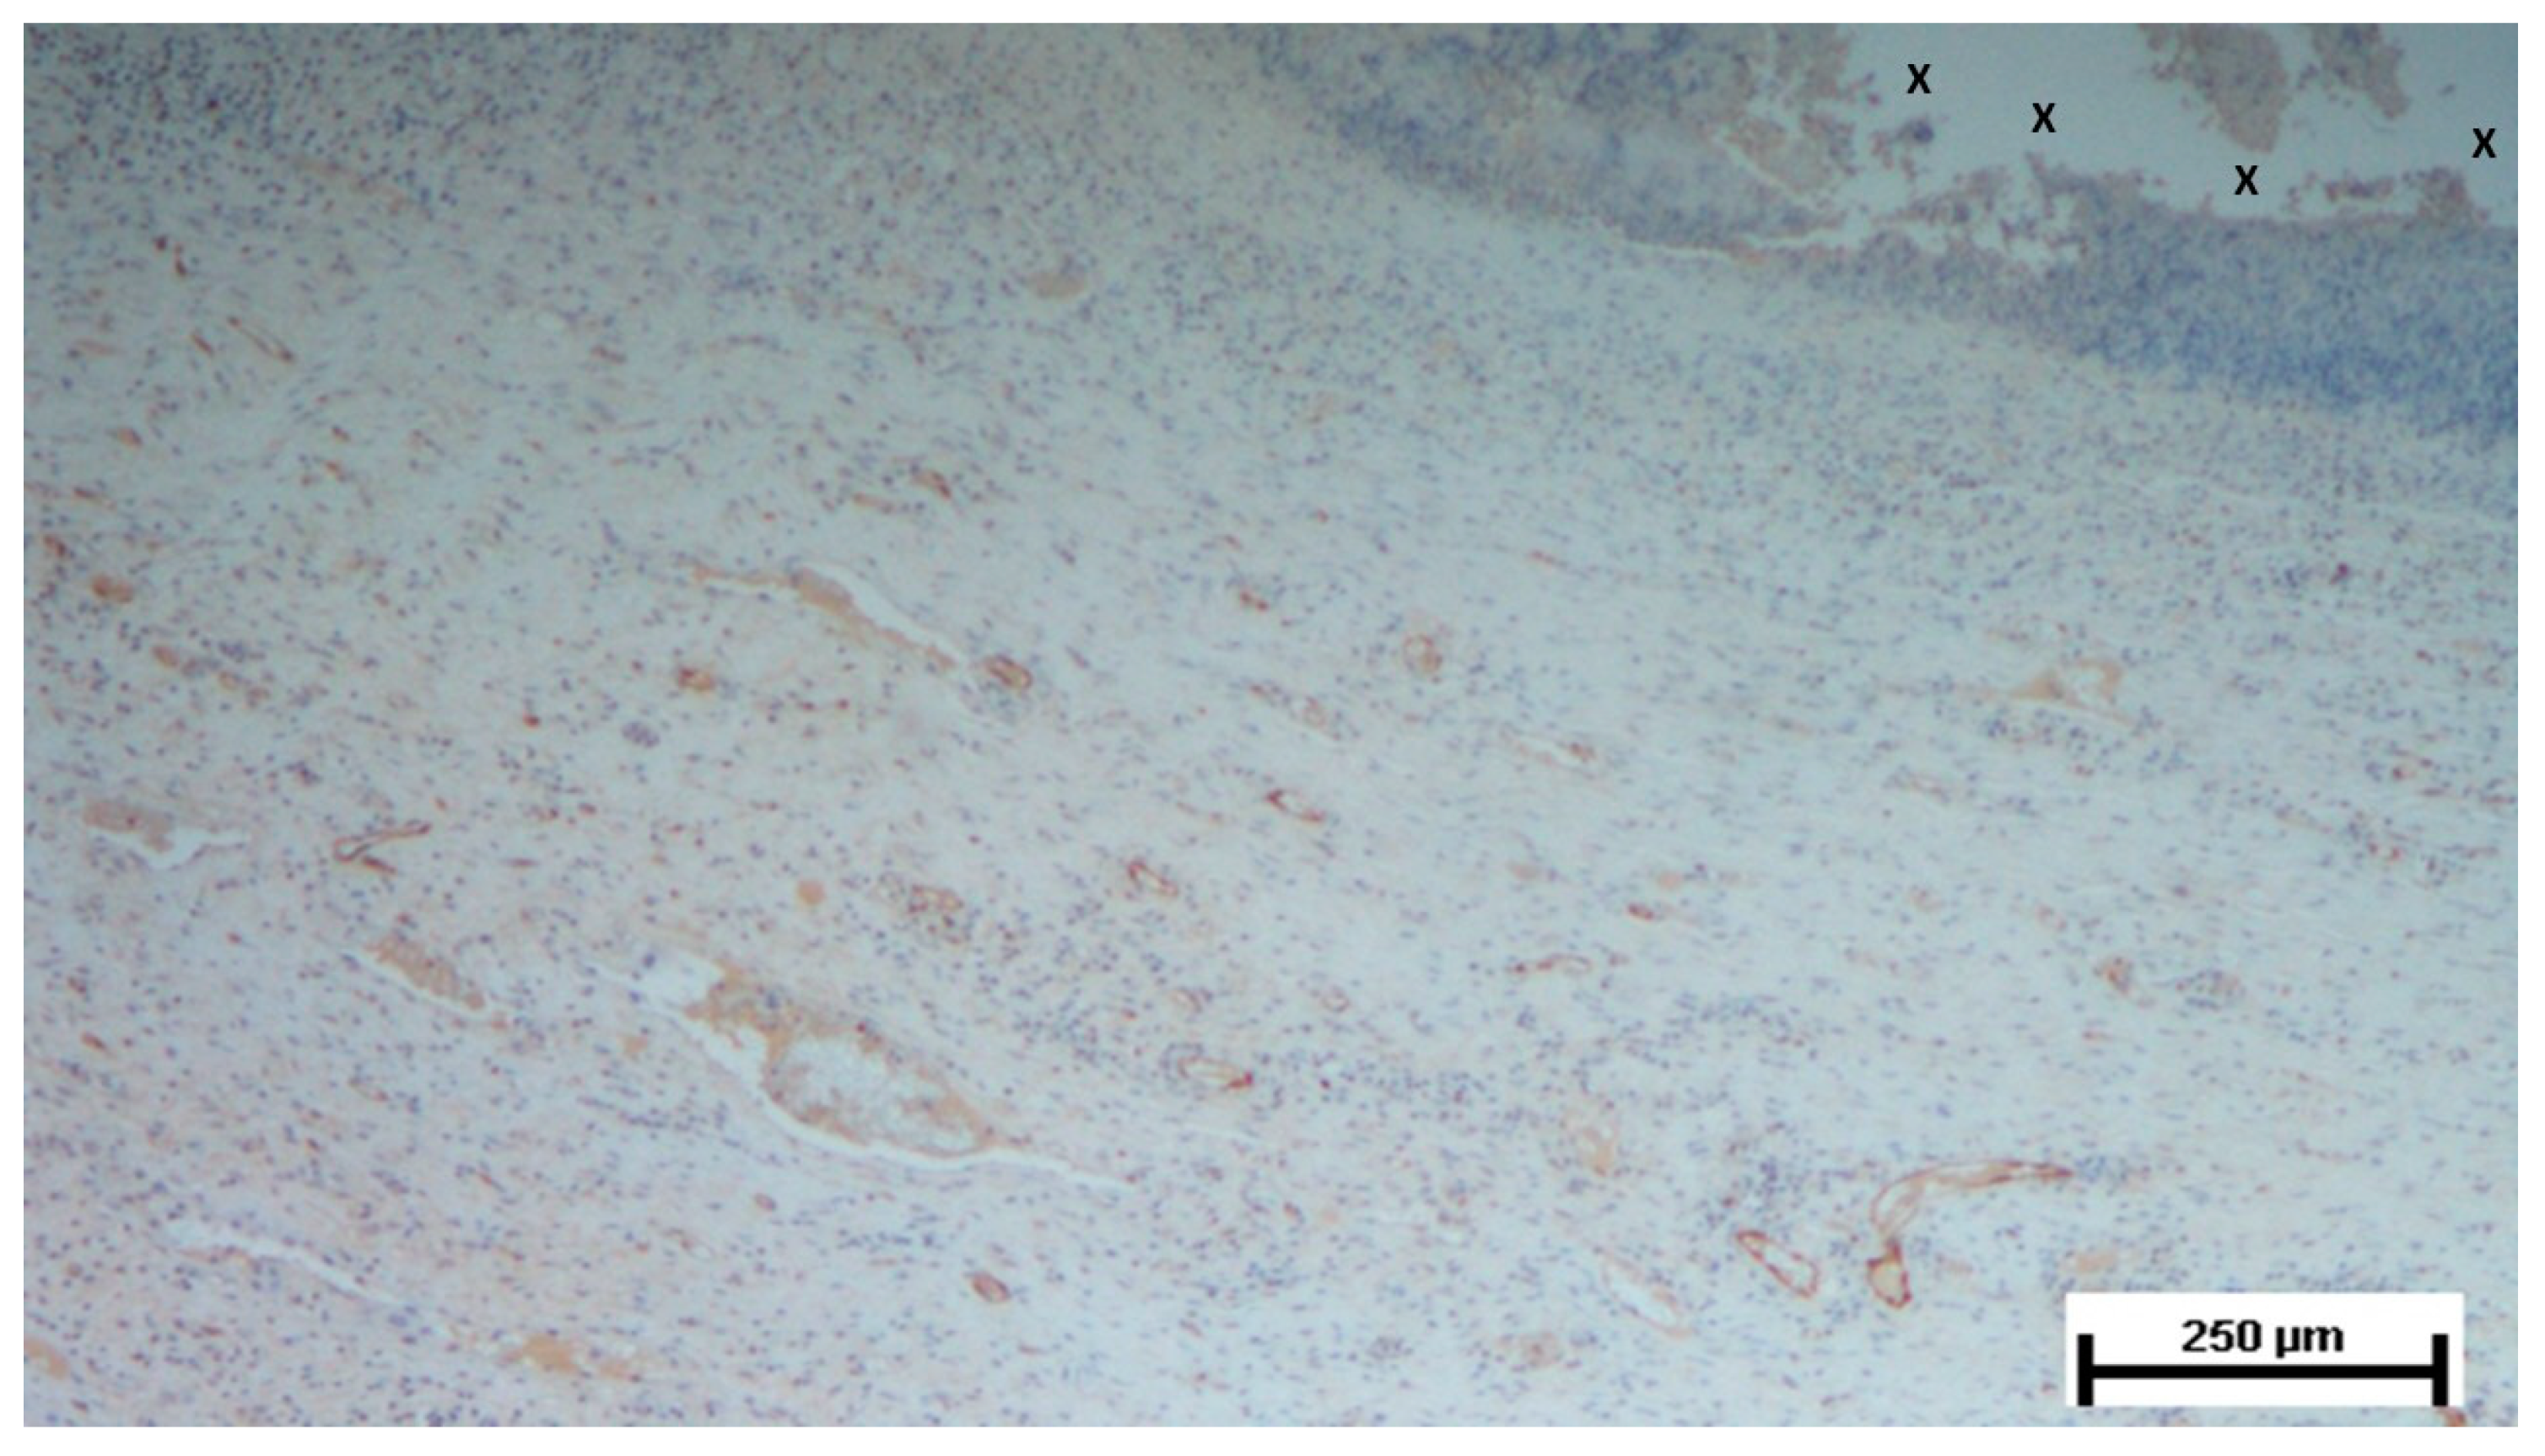

Figure 10. Biopsy taken four months post-implantation from the 3D scaffold of the S&S Hernia System. Numerous vascular elements in advanced stage of development (stained in brown), close to the S&S fabric (X). CD31 50X.

In the mid-term period (3-4 months post-implantation), H&E staining showed a significant presence of vascular structures within the S&S device. Notably, in this postoperative period no signs of inflammatory response against the fabric of the S&S device could be evidenced. The arterial structures displayed advanced development, with well-defined endothelial and muscular layers, while the adventitia was properly enveloping the vessels. Similarly, the veins exhibited noticeable structural maturation compared to the earlier period (Figure 7, Figure 8 & Figure 9).